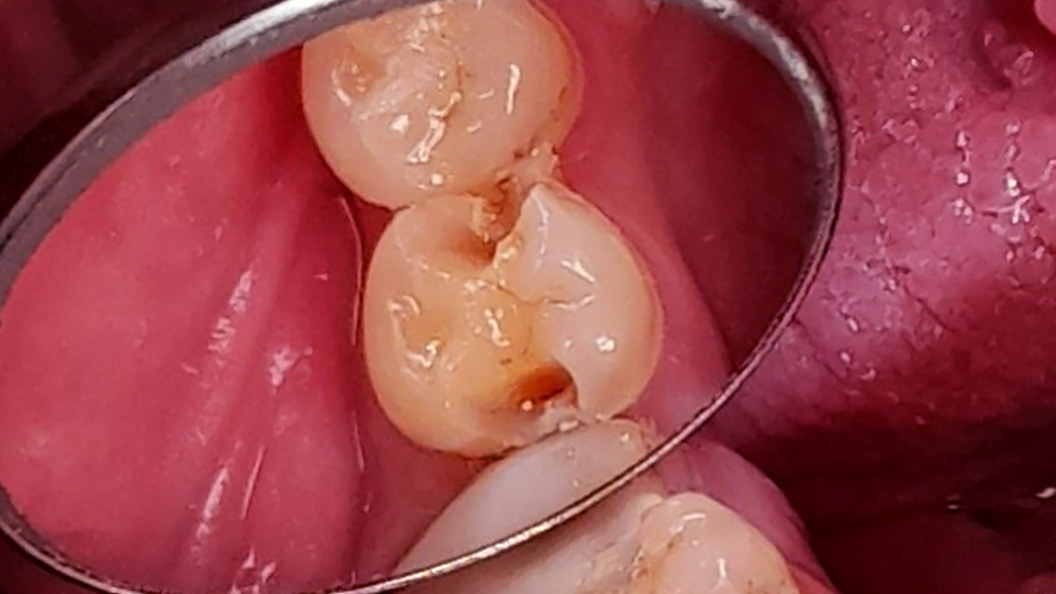

До и после лечения

В «Стоматологию Комфорта» обратился пациент с жалобами на выпадение пломбы из 45 зуба и кратковременные боли от приёма холодных продуктов. Врач-стоматолог-терапевт Похилько Н. Г. в ходе осмотра выявила кариозную полость на мезиально-окклюзионно-дистальной поверхностях 45 зуба. Зондирование было болезненно, перкуссия — безболезненна. Был поставлен диагноз: хронический глубокий кариес 45 зуба. Врач пришёл к выводу о лечении с последующей установкой пломбы из светоотверждаемого композита Estelite.